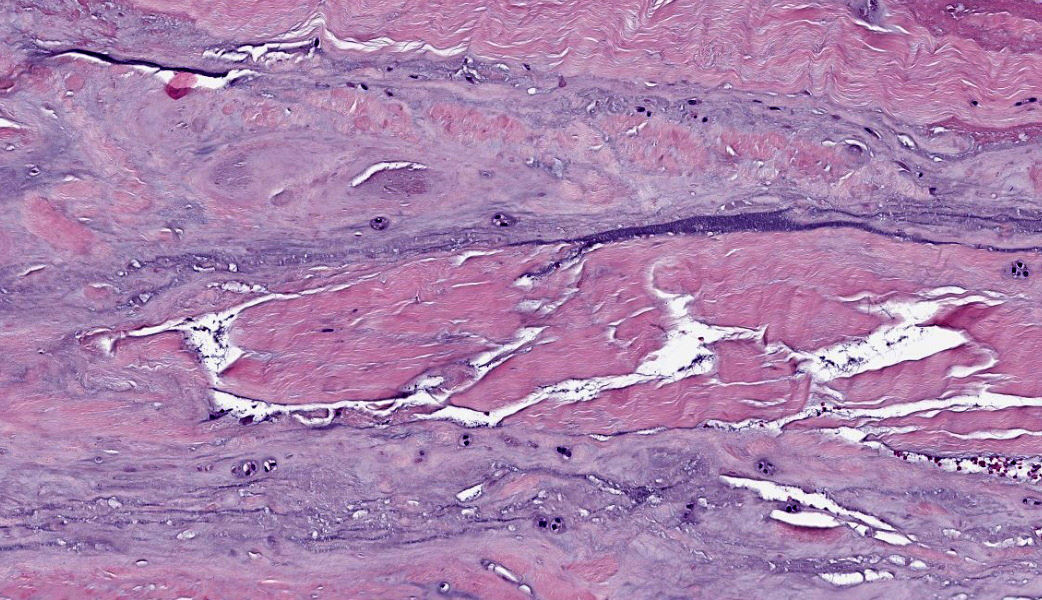

Suspensory ligament, right rear branch. Compared to a branch of the clinically normal right front suspensory ligament, collagen fibers are irregular and often form intersecting or divergent bundles. In many areas, there are fewer fibroblasts among collagen fibers than in the normal control. Throughout the tissue, wavy tendrils of pale basophilic, Alcian blue-positive matrix dissect between collagen bundles. Similar material surrounds increased numbers of variably sized, dilated and tortuous blood vessels. These vessels have thin walls and are lined by plump endothelial cells, and are often surrounded by loosely arranged stellate cells. In other areas, there is chondroid metaplasia, with clustered and individual chondrocyte-like cells in lacunae surrounded by amorphous, pale basophilic matrix, which is sometimes faintly mineralized. There is rare hemorrhage.Contributor's Morphologic Diagnoses:

The terms degenerative suspensory ligament desmitis (DSLD) and suspensory ligament degeneration (SLD) are used somewhat synonymously, with DSLD often used to describe horses with a clinical diagnosis of suspensory ligament degeneration, and SLD used to describe histologic findings in the suspensory ligaments of horses that may or may not have a clinical diagnosis of DSLD. DSLD causes chronic, progressive multi-limb lameness of variable severity, often recognized by enlarged, hyperextended or dropped fetlocks.8 The rear limbs are typically more affected.3,8 In addition, the terms suspensory ligament desmitis or suspensory ligament desmopathy may be used to describe any of a variety of clinically or ultrasonographically detected injuries anywhere along the length of the suspensory ligament.3 Histology is rarely performed in these cases, especially in the acute phase, and it is unclear if these injuries are related to degenerative changes.3Histologic changes in SLD/DSLD include loss of longitudinal arrangement of collagen fibers, proteoglycan accumulation, presence of chondrocytes, hemorrhage, vascular proliferation, and widened interstitial connective tissue septa.4,6 Despite the use of the term desmitis, inflammatory cells are not present.4 These changes are reported to be more severe in the branches of the suspensory ligament than in the body or origin of the ligament.3,5

Ligament: Degeneration, chronic, diffuse, marked, with increased ground substance, vascular proliferation, loss of ligamentocytes, and cartilaginous metaplasia.JPC Comment:

The major histologic findings within ligaments suffering from SLD include loss of longitudinal arrangement of collagen fibers (disorganization), proteoglycan accumulation (increased ground substance), presence of chondrocytes (chondroid metaplasia), hemorrhage, vascular proliferation, widened interstitial connective tissue septae, and a lack of inflammatory cells.8 As this disease develops, regardless of cause, degenerating collagen fascicles blend together and there is either death of the tenocytes/ligamentocytes or metaplasia of tenocytes/ligamentocytes into chondrocytes. Fibrosis develops within and around the ligament and is usually associated with hypertrophied tenocytes/ligamentocytes. These areas are generally interpreted as failed attempts at repair.